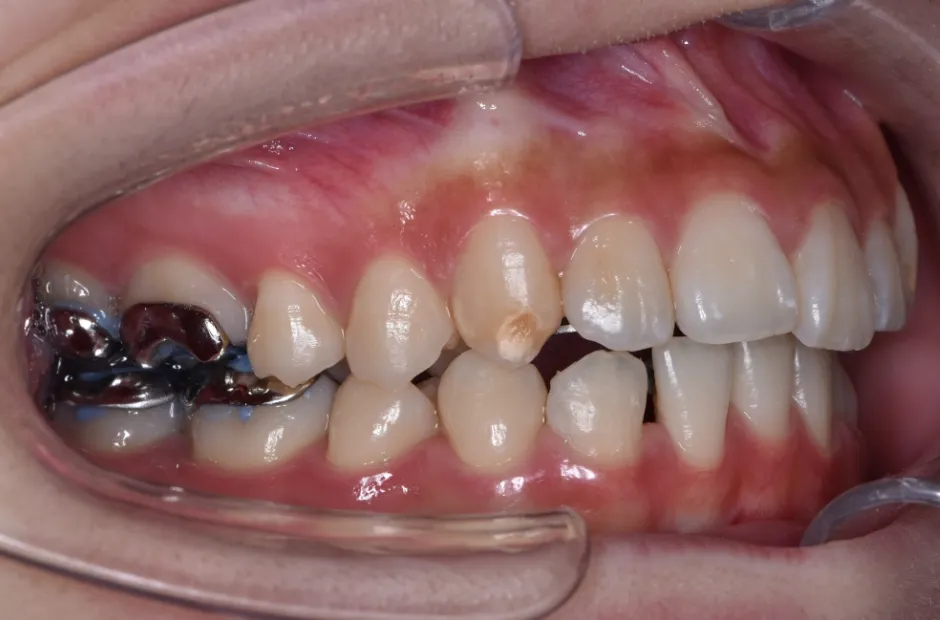

八重歯・でこぼこ・乱ぐい歯

(叢生)

歯が並ぶスペースが足りないために、歯が重なったり前後にずれて生えていたりする状態です。犬歯(八重歯)など目立つ部分の歯列が乱れている場合は、口元の印象に悪影響を与えます。原因としては、遺伝や乳歯の早期抜歯、顎の成長不足などがあげられます。歯磨きが不十分になりやすく、虫歯や歯周病のリスクが高まりやすい不正咬合です。矯正治療を受けると、見た目がよくなるだけでなく清掃性が高まり、お口の健康を維持しやすくなります。

| 診断名・主訴 | 下顎前突、叢生 |

|---|---|

| 年齢・性別 | 23歳・女性 |

| 治療期間・回数 | 3年 |

| 治療に用いた主な装置 | 上顎5,5 下顎4,4 |

| 抜歯部位 | 舌側矯正 |

| 治療費 | 100万円(税抜) |

| リスク・副作用 | 装置による違和感・疼痛・歯肉退縮・歯根吸収・虫歯のリスクなど |